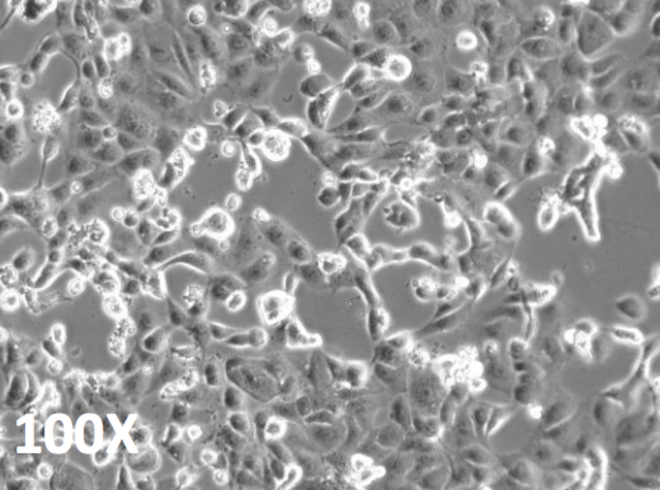

"Avere a disposizione il virus in un sistema di coltura ci permette di provare farmaci in vitro, di avere grandi quantità di virus per la messa a punto di un vaccino e infine avere il virus a disposizione significa poter fare studi di patogenesi, cioè sui meccanismi di replicazione" ha detto Maria Rosaria Capobianchi, direttore del laboratorio di virologia dello Spallanzani. "Sempre quando si scoprono dei virus nuovi il materiale di partenza cruciale è il virus, perché averlo a disposizione significa avere uno strumento per perfezionare la diagnosi e mettere in piedi test sierologici che ancora non ci sono e che significano la ricerca degli anticorpi, quindi la risposta delle persone all'infezione, anche in termini di risposta neutralizzante, ovverosia protettiva, capace di inattivare il virus", ha aggiunto.

La disponibilità nei laboratori del nuovo agente patogeno, inoltre, "permetterà di studiare il meccanismo della malattia per lo sviluppo di cure e la messa a punto del vaccino. La sequenza parziale del virus isolato nei laboratori dello Spallanzani, denominato 2019-nCoV/Italy-INMI1, è già stata depositata nel database GenBank, ed a breve anche il virus sarà reso disponibile per la comunità scientifica internazionale".